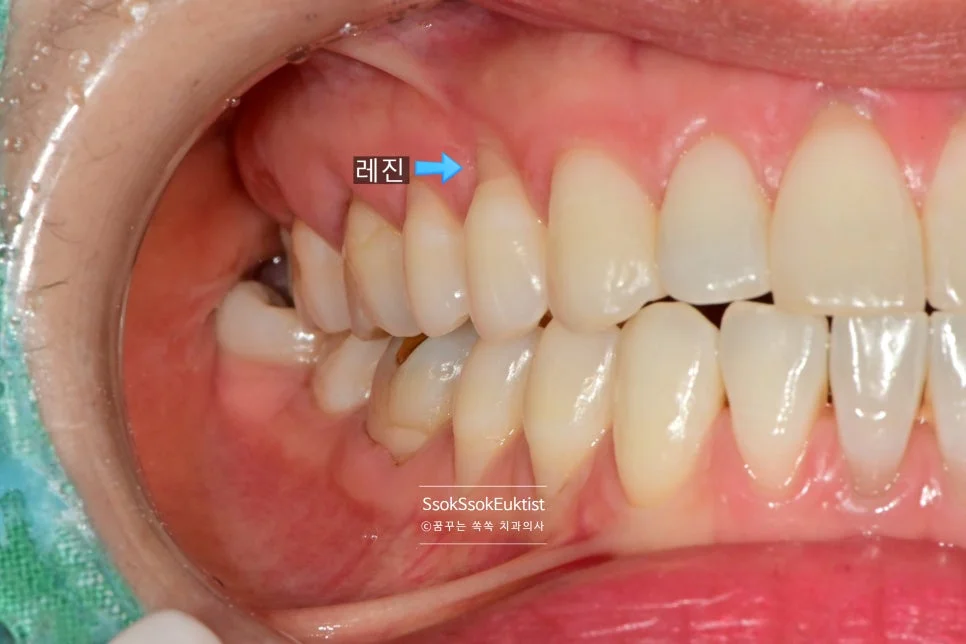

레진과 GI를 둘 다 사용하는 방법은?

GI에 비해 레진이 우수한 점이 1. 색상, 2. 접착력으로 볼 수 있는데요. 그러하다면

으로 치료해도 좋지 않을까요?

6번째 큰 어금니부터는 GI, 5번째 치아까지는 레진으로 진단하고 치료하기도 합니다!

화살표로 표기된 치료 계획 — 앞쪽은 레진, 어금니는 GI

화살표로 표기된 것과 같이 눈에 보이는 앞 쪽 치아는 레진으로, 큰 어금니는 GI로 계획을 세웠는데요.

결과는 과연 어떻게 되었을까요?